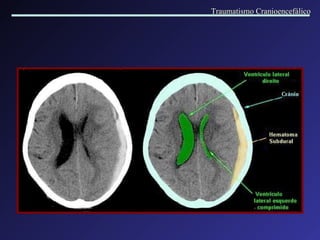

Hemorragia Extra axial Hematoma Subdural Agudo   Formados entre a duramater e a aracnóide, por lesão de veias córtico-meníngeas. Este espaço é facilmente dilatável, possibilitando grandes acúmulos de sangue. Causas: quedas ou agressão. Lesões associadas. Intervalo lúcido. Coleção em crescente, com efeito de massa variável. A cirurgia normalmente está indicada. Traumatismo Cranioencefálico

Hematoma Subdural   Agudo Traumatismo Cranioencefálico

Traumatismo Cranioencefálico

Hematoma Subdural Agudo em regiões fronto-temporo-parietal D, com importante desvio da linha mediana (tumefação hemisférica) e hematoma epidural associado na região parietal E. Traumatismo Cranioencefálico

Hematomas subdurais bilaterais, com diferentes idades (crônico à direita e agudo à esquerda), associados a atrofia . Hematomas subdurais bilaterais agudos. Traumatismo Cranioencefálico